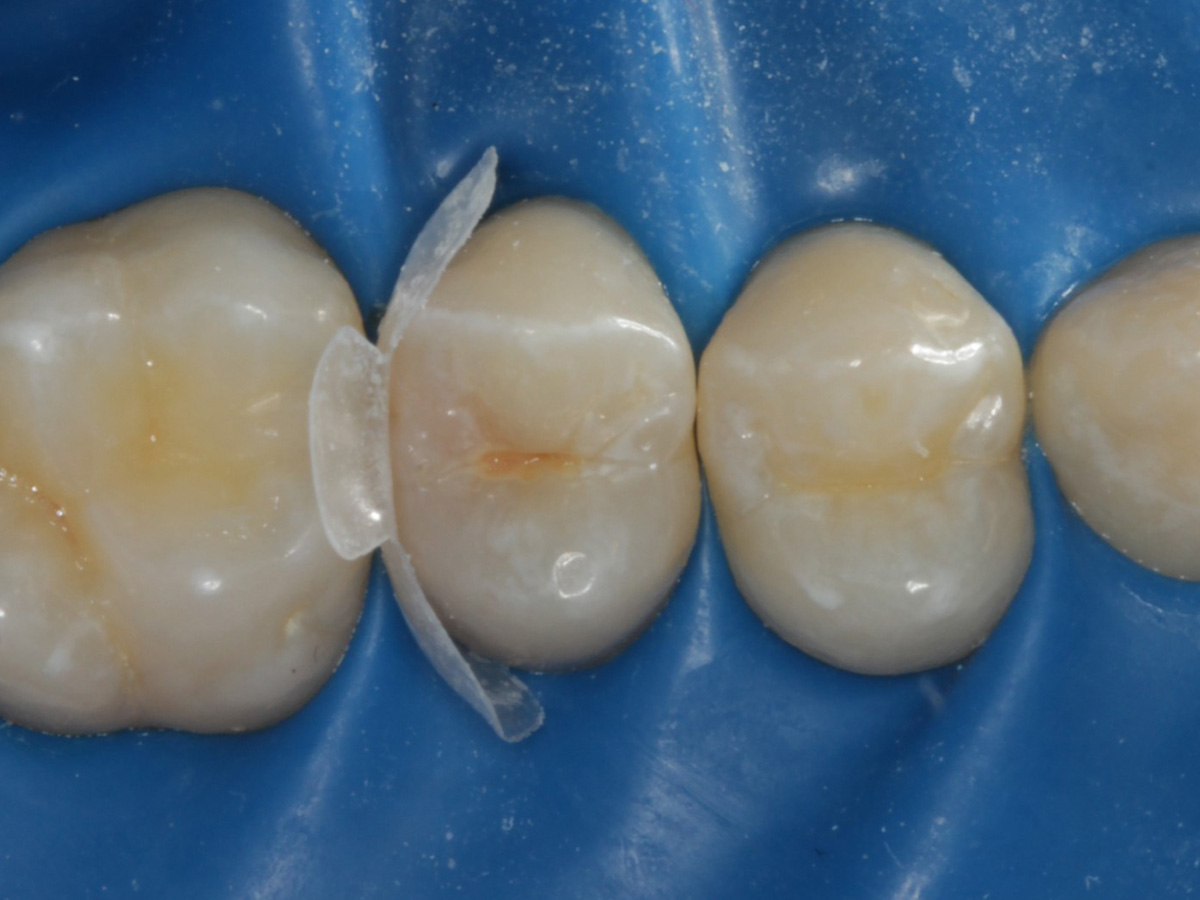

Abbildung 2

Intakte Kaufläche